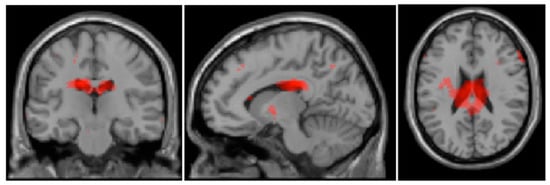

| Cluster | Cluster-Size | Brain Regions | Hemisphere | BA | MNI-Coordinates (x, y, z) | T | ||

|---|---|---|---|---|---|---|---|---|

| Guilt: BPD patients > healthy controls | ||||||||

| 1 | 2302 | Nucleus caudatus | L | * | −12 | −22 | 28 | 6.22 |

| Gyrus cinguli | L | 23 | −4 | −12 | 24 | 4.62 | ||

| Gyrus cinguli | R | 23 | 12 | −16 | 26 | 4.16 | ||

| 2 | 890 | Gyrus fusiformis | R | 19 | 32 | −80 | −10 | 4.38 |

| Pyramis (CB) | R | * | 14 | −80 | −26 | 2.92 | ||

| Declive (CB) | R | * | 6 | −82 | −20 | 2.37 | ||

| 3 | 872 | Declive (CB) | L | * | −28 | −82 | −14 | 3.76 |

| Gyrus occipitalis inferior | L | 19 | −44 | −82 | 2 | 3.62 | ||

| Gyrus fusiformis | L | 19 | −46 | −76 | −8 | 2.78 | ||

| Guilt: Healthy controls > BPD patients | ||||||||

| 1 | 7154 | Cuneus | R | 18 | 6 | −78 | 24 | 4.05 |

| Gyrus lingualis | L | * | −14 | −74 | 6 | 4.02 | ||

| Gyrus lingualis | R | 18 | 16 | −68 | 2 | 4.00 | ||

| 2 | 1279 | Gyrus praecentralis | R | 6 | 62 | 2 | 22 | 3.73 |

| Gyrus praecentralis | R | 4 | 52 | −12 | 44 | 3.00 | ||

| Gyrus postcentralis | R | 4 | 62 | −10 | 32 | 2.86 | ||

| 3 | 838 | Gyrus temporalis superior | R | 22 | 64 | 14 | −8 | 4.03 |

| Gyrus temporalis superior | R | 38 | 62 | 14 | −16 | 3.40 | ||

| Uncus | R | 36 | 24 | −4 | −34 | 3.24 | ||